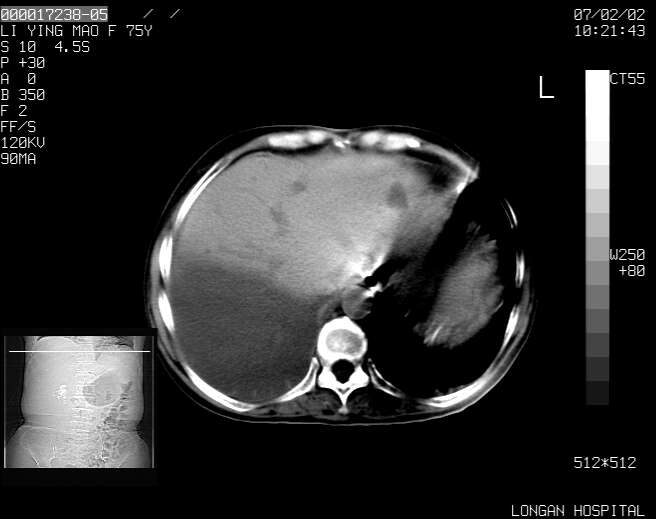

以下是引用dyqct在2007-2-10 8:53:00的发言:[br]考虑:1、肝脏多发囊肿[br] 2、左肾囊肿,右肾多发结石并积水。[br] 3、右胸少量积液。[br] 4、右肾周包裹性积液或淋巴管瘤(有见缝就钻的征象、薄隔、小结节状钙化)?[br] 5、腰椎动脉瘤样骨囊肿?[br] [br] [br]